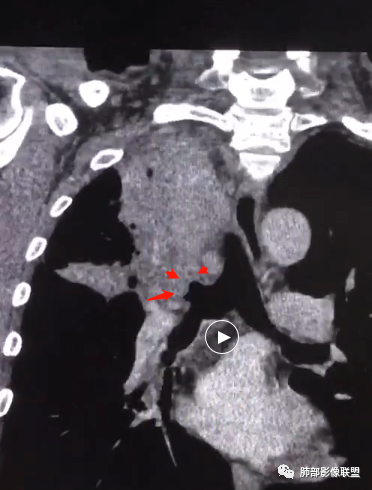

形态、边缘、支气管、血管、密度及强化(坏死腔内壁)、淋巴结、与胸膜关系、附近病灶,大概这些分析点

这类病变最好重建出长轴、支气管,这样观察就比较理想

影像上其实也有特点,需要重建观察到支气管情况

这是炎性的,支气管壁弥漫增厚,近端腔狭窄

这是肺癌的

这是腔内肺癌的

南边:

1、局部占位效应,支气管往往增大,而不是支气管狭窄

2、支气管壁破坏、不连续,腔外侵犯

3、占位效应大,局部肺动脉受压外移或侵犯

局部肺动脉没看清楚,支气管壁我没看清楚。占位效应有,这是最不踏实的地方。